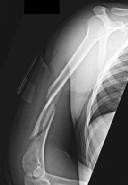

Question 9:

A 72-year-old female on prolonged bisphosphonate therapy presents with thigh pain. Radiographs show a fracture of the femoral shaft. Which of the following radiographic features is most characteristic of an atypical femur fracture associated with bisphosphonate use?

Correct Answer: Transverse or short oblique fracture line originating at the lateral cortex with localized periosteal thickening (beaking)

Explanation:

Atypical femur fractures (AFFs) associated with prolonged bisphosphonate therapy have specific major criteria defined by the ASBMR. These include a location anywhere from just distal to the lesser trochanter to just proximal to the supracondylar flare, transverse or short oblique orientation, non-comminuted (or minimally comminuted), and originating at the lateral cortex with localized periosteal or endosteal thickening ('beaking').